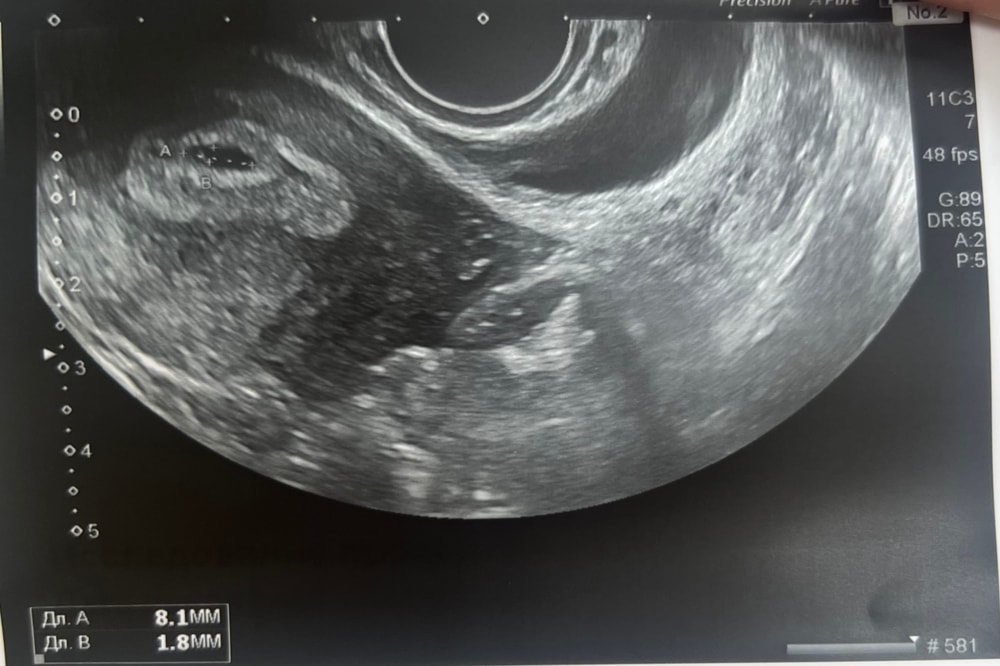

В итоге нашли плодное яйцо 8мм, желточный мешок 1,8мм 🥹 срок 5-5,5 недель

а по календарю 5н4д

желтое тело 19мм, малышарик прикрепился по передней стенке матки)